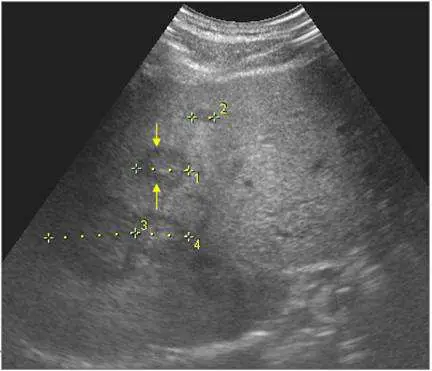

大腸癌病人,定期追蹤肝臟超音波掃描如下圖,箭號所指最可能為何? 圖片

超音波影像顯示肝臟實質內有兩個低回音性(hypoechoic)病灶(黃色箭號所指,並附有測量游標 1、2、3、4),呈現以下特徵:

• 低回音中心:病灶核心相對於周圍肝臟實質呈明顯低回音

• 周圍低回音暈環(hypoechoic halo / target sign):病灶外圍可見一圈低回音暈,使整體呈現「牛眼(bull's eye)」或「靶心(target)」外觀

• 邊界不清:與周圍正常肝實質的界面相對模糊,非銳利清晰

• 不均質回音:內部回音不均勻,非純液性

• 無後方增強:排除囊性病灶(如肝膿瘍液化腔)

此種「實質性低回音病灶+周圍暈環」的表現,在有大腸癌病史的病人中,高度提示肝內轉移癌。